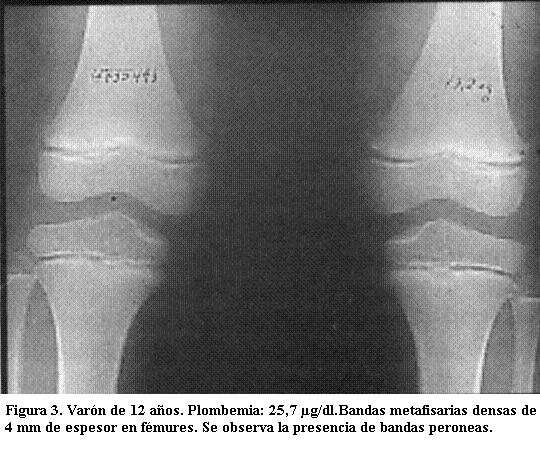

Predominan en las de crecimiento más rápido (las ubicadas en rodillas y muñecas) incluido el peroné, signo de importancia ya que otras enfermedades que producen bandas densas metafisarias no afectan este hueso (3).

Tienen varios milímetros de espesor y sus límites son nítidos. Son tanto más densas cuanto mayor sea el grado de absorción del metal y tanto más anchas cuanto más haya durado el proceso de absorción (figuras 3, 4 y 5) (5).